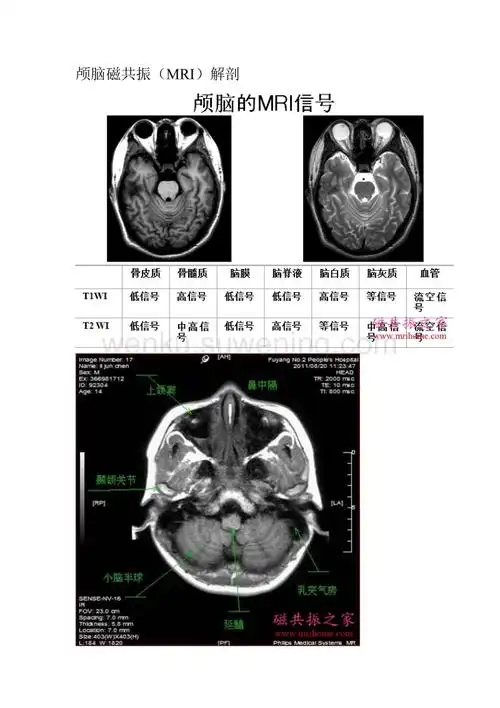

颅脑轴位mri解剖